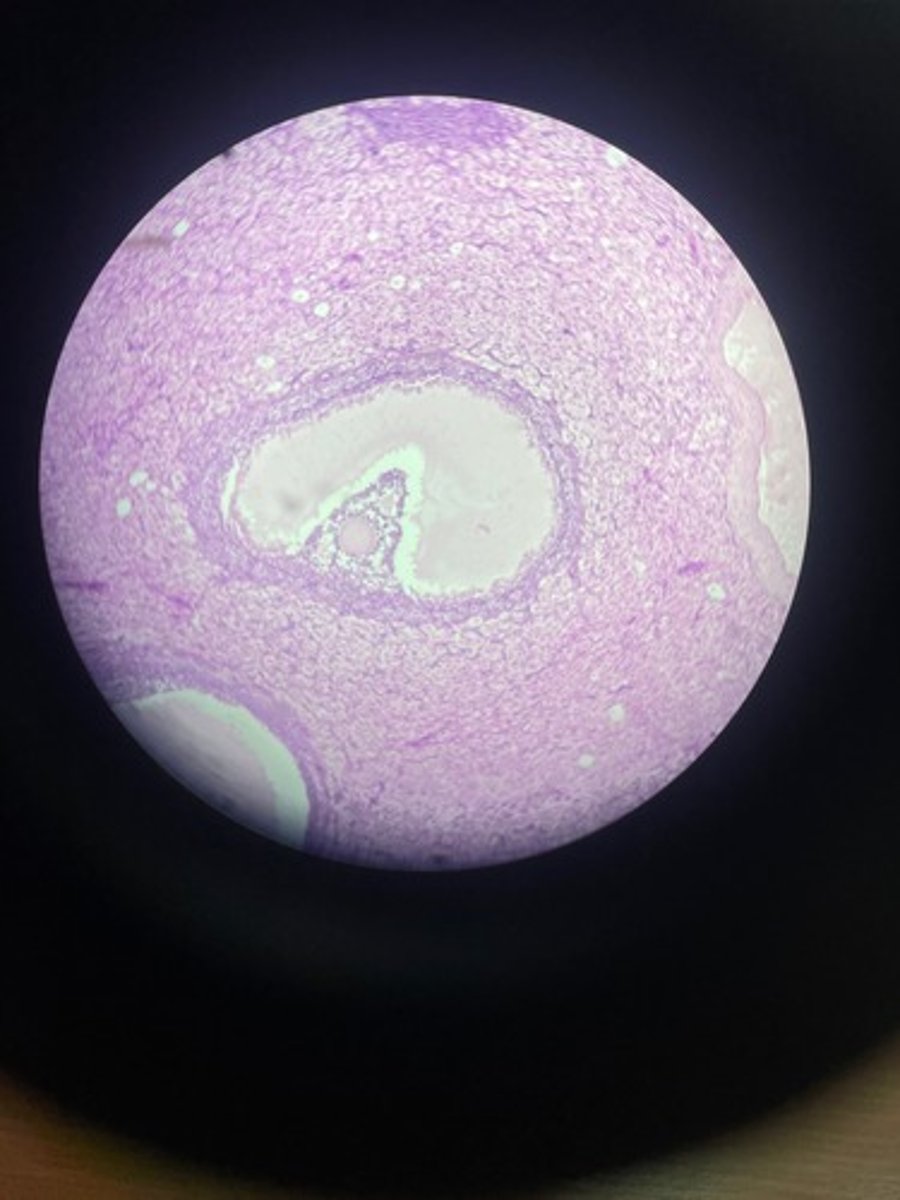

Kidney HE

Kidney HE

Kidney HE

Kidney HE

Kidney HE